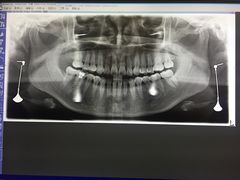

• 耀光牙科(南园店)

• -耀光牙科(南园店)